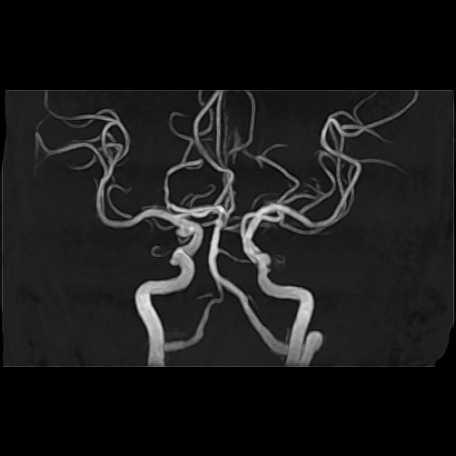

頭部

脳動脈瘤